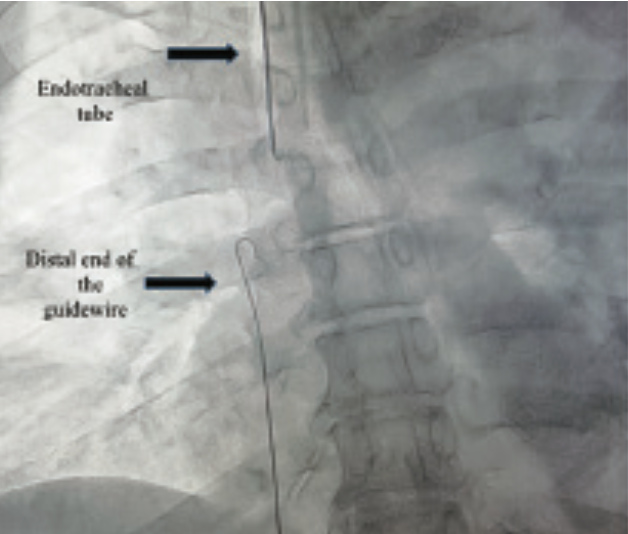

This case involves a 59-year-old male with a diagnosis of SARS-CoV-2-confirmed atypical pneumonia (Covid-19) under invasive mechanical ventilation, vasopressor support with norepinephrine, and hemodynamic surveillance with an arterial line located in the right femoral artery and a central venous catheter located in the right femoral vein. He presented with acute kidney injury. It was decided to substitute treatment for kidney function with continuous renal replacement therapy, so a hemodialysis catheter was placed for left femoral venous access; however, during its placement, there was an accidental migration of the guidewire. Guidewire recovery was requested of the interventional cardiology department.